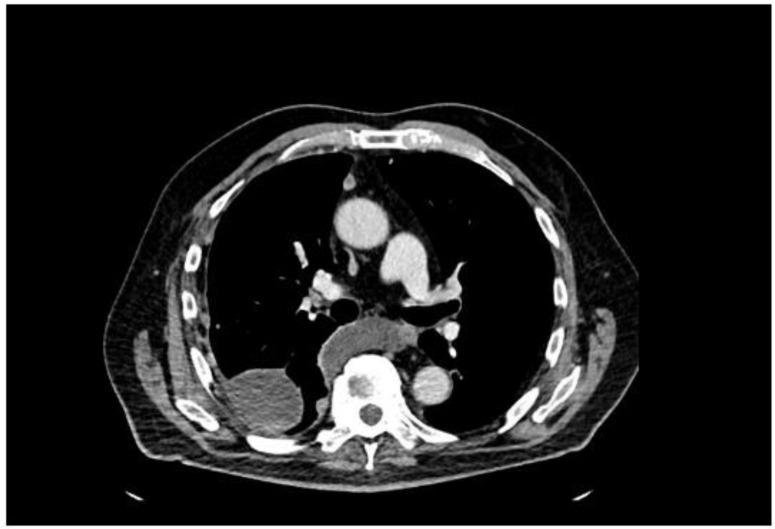

我们描述了一名77岁男性,他出现劳力性呼吸困难和间歇性咳嗽,最初提示心肺病因。影像学检查发现多个胸膜结节和广泛的右侧胸腔积液。尽管血清前列腺特异性抗原(PSA)水平临界为2.91 ng/mL,但胸膜活检的组织病理学和免疫组化结果证实为转移性前列腺腺癌。随后的影像学检查在前列腺中发现了一个PI-RADS 5类病变,活检证实为ISUP 5级组疾病(Gleason评分4 + 5 = 9)。骨扫描显示无骨转移,腹部增强CT未发现其他转移病灶。患者开始接受雄激素剥夺治疗,随后使用阿比特龙。该病例强调了前列腺癌非典型转移表现所带来的诊断挑战。低或中度升高的PSA可能会掩盖对前列腺起源的怀疑,尤其是对于提示间皮瘤的胸膜病变。包括雄激素受体、AMACR和Prostein在内的免疫组化标志物对于准确诊断至关重要。